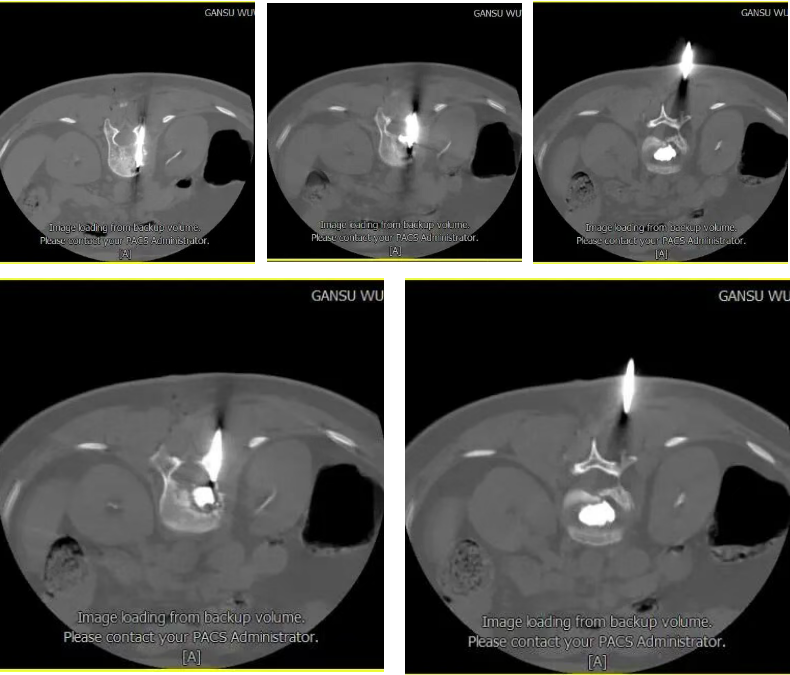

E:优骨水泥注射结束后,拔除穿刺针后再次扫描,确定骨水泥注射后情况。

4、术后观察:确认骨水泥凝固且无渗漏后缝合创口。

患者经过治疗进行疼痛评估和脊柱功能评估提示,患者疼痛严重程度明显下降,腰椎活动度较治疗前好转。